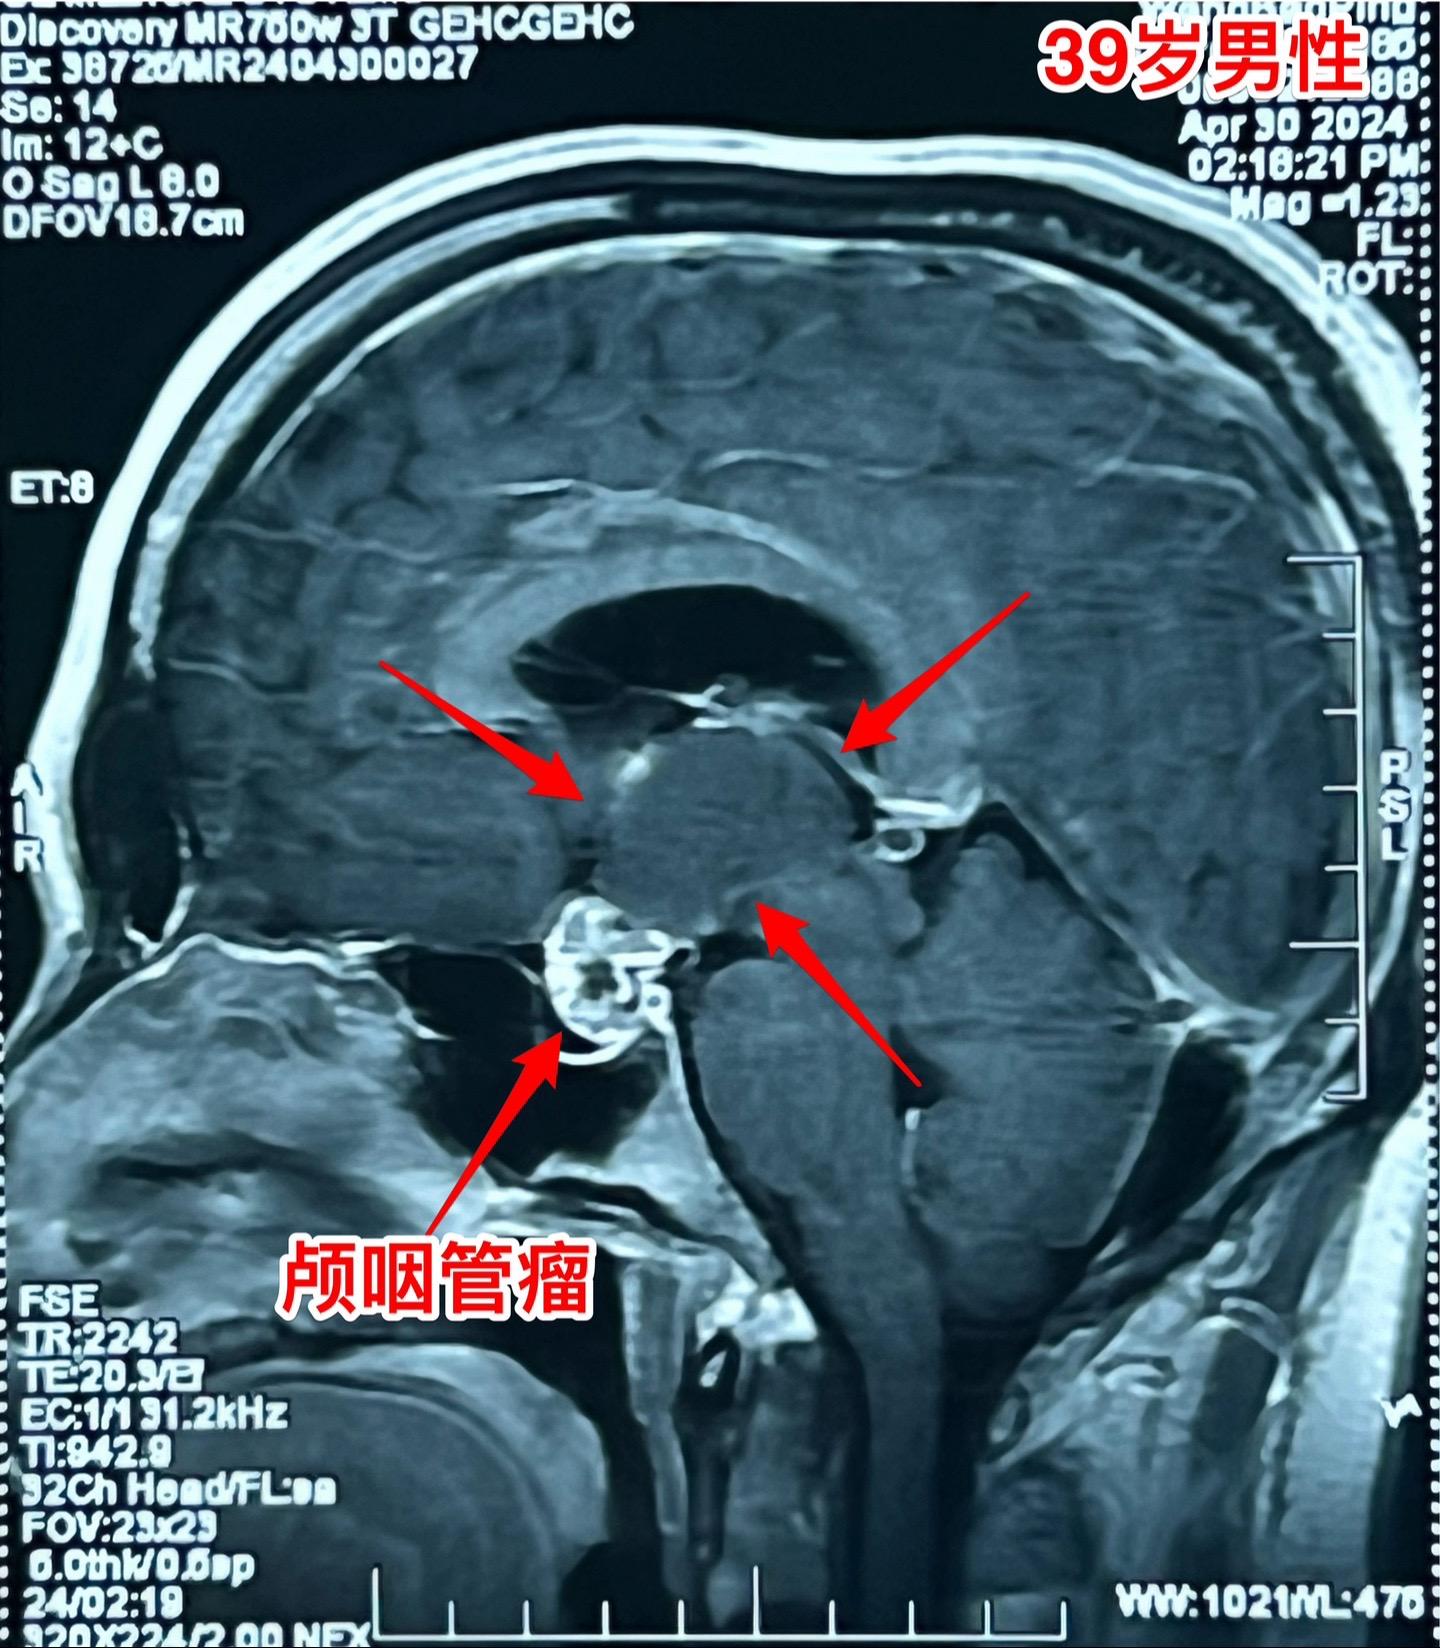

五月六日的颅咽管瘤手术。山西省男性,39岁,因为头痛、呕吐在4月29日就急匆匆的赶到三博脑科医院来住院。病因是颅咽管瘤造成颅压高,不能正常吃东西了。住院后用药物治疗,头痛症状减轻,也不呕吐,能正常进食。从图片可以看出这个颅咽管瘤属于细长型,从垂体窝延伸到第三脑室内,垂体窝里有大块钙化,手术是有难度的。 五一假期一过就排上手术,顺利切除肿瘤,手术后CT结果很让人满意,希望肿瘤不复发。